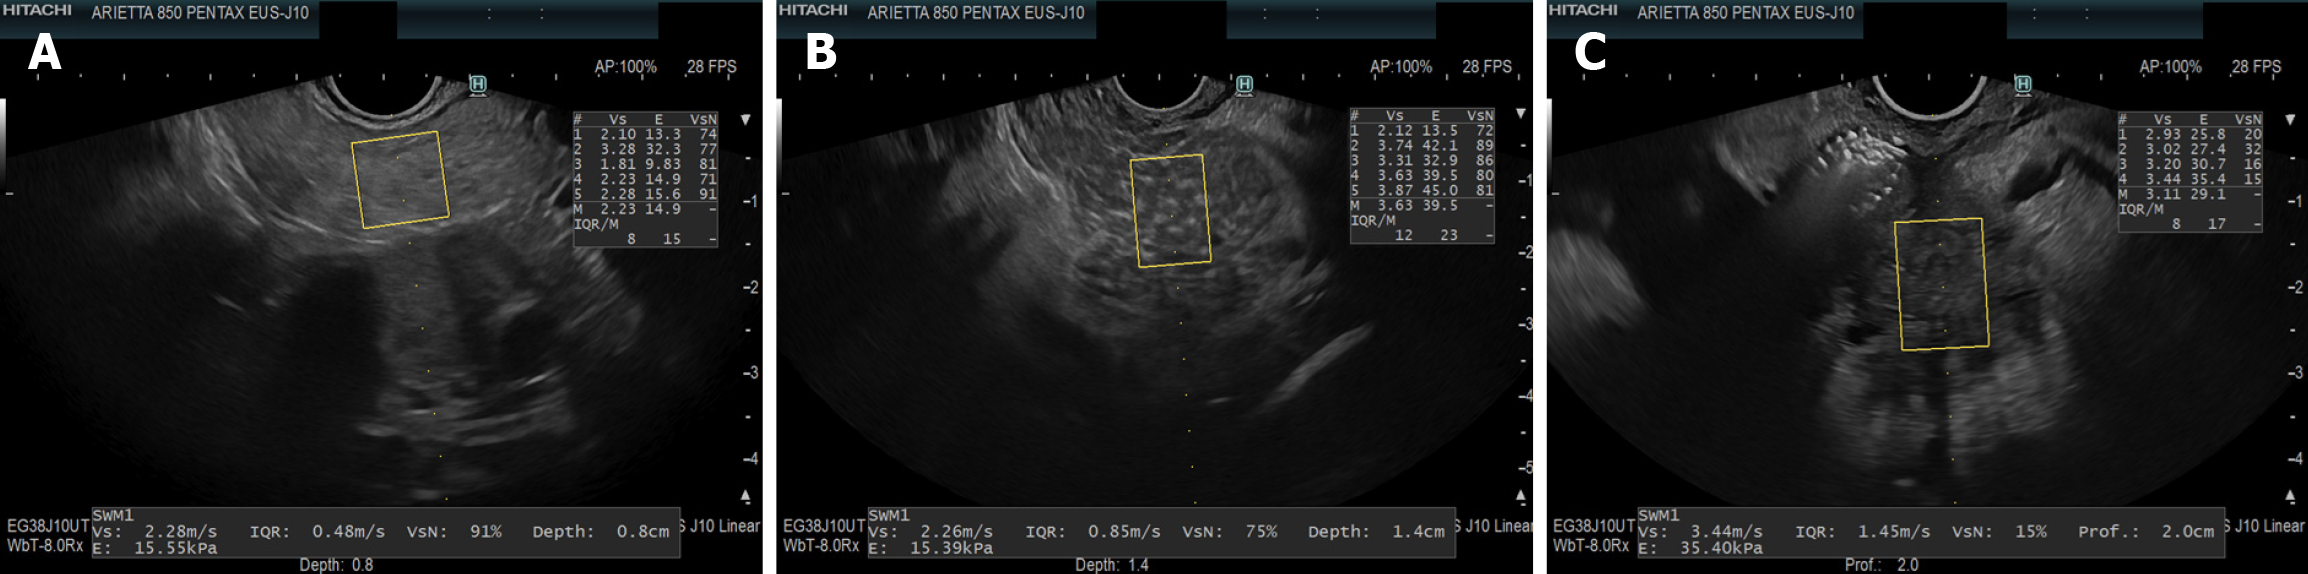

Figure 2 Endoscopic ultrasound-guided shear wave elastography images.

A: Normal liver; B: Cirrhotic liver; C: Spleen. In endoscopic ultrasound-guided shear wave elastography, shear wave velocity is higher in cirrhotic liver compared to normal liver, reflecting increased parenchymal stiffness. Spleen stiffness measurements may provide additional information on the degree of portal hypertension.